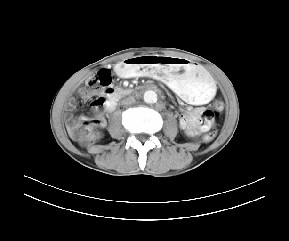

标题: CT19533:病变来源于哪?

患者,男,发现上腹部包块两月余。

病变位于肝胃间隙,实际就是位于小网膜囊(左肝下后间隙),呈轻度不均匀性强化,腹腔内及腹膜后见多发肿大淋巴结。所以我考虑肝胃间隙恶性胃肠间质瘤并淋巴结转移。

病灶强化不显著,灶周及腹膜后见多量淋巴结肿大,考虑淋巴瘤可能,其次考虑间质瘤

病灶与胰腺分界不清,来源于胰腺?

强化后病变与胃壁分界清楚,并且血供不是来源胃壁血管。考虑胰腺颈体癌并腹腔腹膜后淋巴结转移。